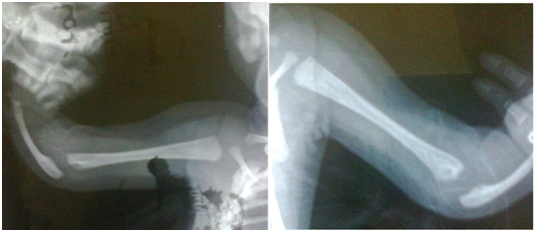

A newborn infant with congenital absence of the radii without thumb aplasia (Figure 1) was observed. Absence of the radii was shown on radiograph (Figure 2). The neonate was followed for one week without the occurrence of thrombocytopenia. The rest of physical examination was normal and no other abnormalities could be detected. The parents were consanguineous, but family history was negative for a similar condition.

Figure 2 Radiograph showing absence of the radii.